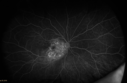

13 year old who was hit in the right eye with a softball about 2 years ago. Pain but no vision loss then. Got "blurry" OD about 5-6 months ago VA OD: Dcc20/40-2 NccJ2 VA OS: Dcc20/20

Choroidal Osteoma 13 Year Old565 views13 year old with 6 months of vision loss right eye and vision of 20/4000000